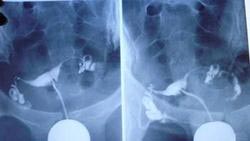

热点探究:输卵管造影疼不疼?

输卵管造影术 给您“畅通无阻”的幸福

· 东吴专家为您讲解:输卵管造影

· 临床证实:输卵管造影是检查输卵